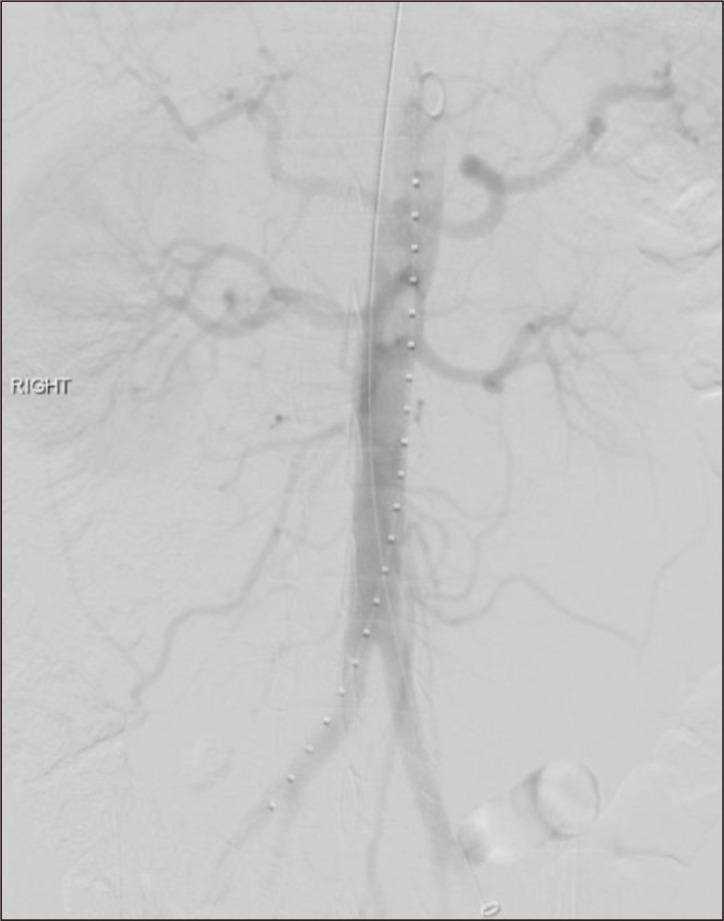

Spontaneous aortic thrombosis is exceedingly rare, and optimal treatment remains uncertain. We present an unusual case of a spontaneous aortic thrombus at the renal artery level in a patient undergoing active cisplatin treatment for urothelial carcinoma. Management included catheter-directed thrombolysis followed by thrombectomy. An open cutdown was performed on the left common femoral artery (CFA), with right groin access via a 6-Fr sheath. Clamping of the left superficial and deep femoral arteries, along with balloon occlusion of the right common iliac artery, prevented distal embolization. A Coda balloon introduced via direct left CFA puncture with a 20-Fr sheath was positioned above the aortic thrombus. After inflation, clots were trawled to the sheath, "sandwiching" the clots before removal of the balloon and sheath via the left groin. Post-operatively, the patient recovered well and received continued therapeutic anticoagulation.

自发性主动脉血栓形成极为罕见,最佳治疗方法仍不明确。我们报告了一例不寻常的病例,一名正在接受顺铂治疗尿路上皮癌的患者在肾动脉水平出现自发性主动脉血栓。治疗措施包括导管定向溶栓,随后进行血栓切除术。在左股总动脉(CFA)进行开放切开,通过一个6F鞘管进入右腹股沟。夹闭左股浅动脉和股深动脉,同时球囊封堵右髂总动脉,防止远端栓塞。通过直接经20F鞘管穿刺左CFA引入的Coda球囊置于主动脉血栓上方。球囊充气后,将血栓拖至鞘管,在通过左腹股沟移除球囊和鞘管之前对血栓进行“夹取”。术后,患者恢复良好,并继续接受抗凝治疗。